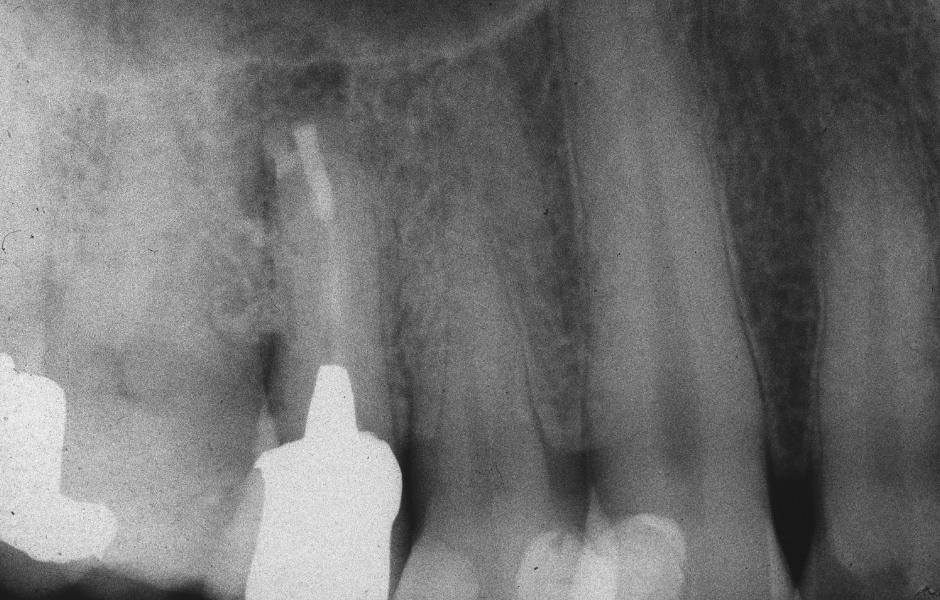

Obr. 2.8: Pooperační rentgenový snímek zobrazující obě retrográdní výplně.

Obr. 2.9: Kontrola po třech letech s kompletním zhojením obou lézí.

Obr. 4.1: Předoperační snímek horního levého prvního moláru. Oba kanálky mesiobukálního kořene byly kompletně kalcifikované a nebylo možné je ortográdně zprůchodnit.

Obr. 4.4: Pooperační rentgenový snímek zobrazující retrográdní výplň z bílého MTA.

Obr. 4.6: Kontrola po třech letech se zhojením léze.